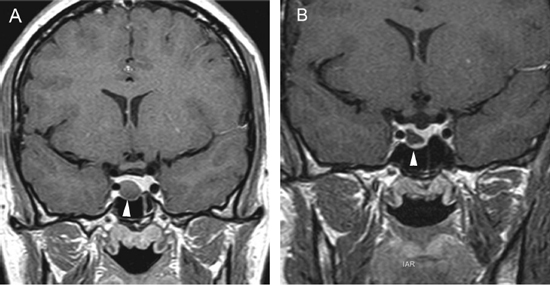

En los tumores grandes (macroadenomas) la TAC puede entregar información diagnóstica adecuada, pero no supera la definición que se logra con equipos de RM superconductores (Figuras 2 A y 2B).

Figura 2A y B. Cortes sagitales de RM y TAC. Adenoma pituitario con invasión del esfenoides y del clivus (puntas de flecha). Es posible demostrar las estructuras óseas en RM con similar precisión que la TAC.